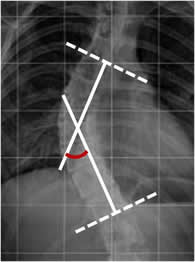

El ángulo de Cobb es la medición mas aceptada y confiable, para medir las desviaciones en el plano coronal. Se traza por la intersección de las líneas perpendiculares, al borde superior de la vértebra límite proximal y el inferior de la distal. (1, 3, 8, 25, 26). (Fig 28 y 29).

En esta medición hay mucha variación intra e interobservador, de hasta 5-10º. Es importante informar que vértebras se tomaron de referencia al trazar las líneas, para hacer los futuros controles. (3,8, 26).

Un incremento de 5º o mas en Rx sucesivas, indican progresión y requieren manejo. (8, 25, 26). (Fig 30). Se puede incurrir en un error de estabilidad, si se compara con la proyección mas reciente. Significativa progresión se puede detectar, al comparar con los estudios iniciales. También es importante comparar el grado de rotación de la vértebra apical y la variación en el nivel de las crestas iliacas. (25).

Fig 28. Angulo de Cobb.

Rx AP. Trazado entre las perpendiculares sobre el borde superior de la vértebra límite proximal y el borde inferior de la vértebra límite distal.